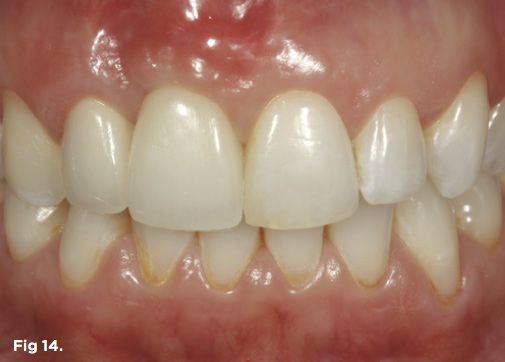

Fig 14. The definitive restoration, a tooth No. 7 crown splinted to implant crown No. 8, shows harmony in regard to the natural dentition as well as the reconstructed gingival architecture, which was improved employing forced orthodontic tooth eruption.

Figure 14

After 6 months of healing of the implant, stage 2 uncovering was performed and the mucosal tissues were allowed to mature for another 2 to 3 weeks. A temporary screw-retained implant cylinder was joined to the implant and acrylic crown (Figure 8). The subgingival shape of the temporary was modified with additional acrylic and the technique of non-surgical tissue sculpting, which was developed to provide the proper emergence profile to the mucosal tissues.27 It is important that the temporary blanching (ischemia) of the mucosal tissues dissipate after 10 minutes (Figure 9). After 3 weeks, soft-tissue scalloping through gingivectomy was done to recreate the proper shape (ie, gingival zenith)28 and proportion for the mucosal tissues (Figure 10). Fiberotomy on the distal aspect of tooth No. 7 was not performed during treatment; therefore, this papilla was slightly more incisal (longer) than the adjacent papillae (Figure 11). A final impression was made of crown No. 7 and implant No. 8 at the implant level to enable a working cast to be made in the laboratory. An all-ceramic custom abutment was made for implant No. 8, and splinted full-coverage units were made for crowns No. 7 and No. 829 (Figure 12). The custom abutment was seated intraorally and torqued according to the manufacturer’s recommendation. The crowns were luted with provisional cement and maintained at 4-month recall intervals (Figure 13). Note the health of the periodontal tissues and its integration with the adjacent teeth and surrounding gingiva, taking a complex esthetic and functional problem for a patient with a high smile line and providing a predictable restorative and esthetic outcome (Figure 14).